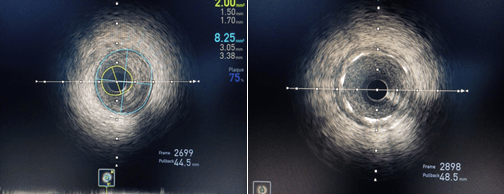

术前IVUS示最小管腔面积2.00mm2;术后IVUS示最小支架面积7.61mm2